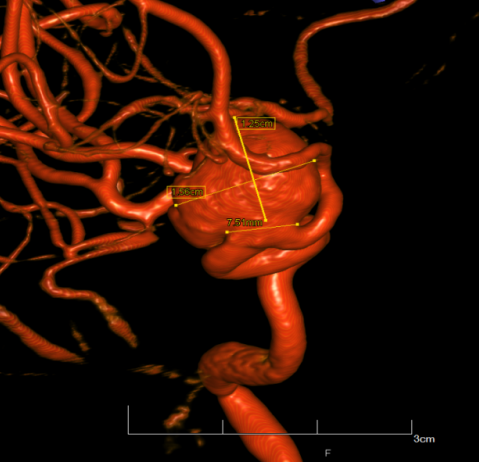

syngo Dyna4D展示特定时间点上的3D图像,对于脑血管畸形、血管瘤、动静脉瘘的结构、位置,并测量尺寸、分析供血动脉和引流静脉等。